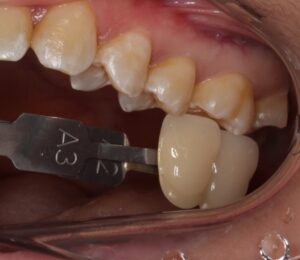

歯の色見本を照らし合わせ、その方の歯の色に合ったセラミックを歯科技工士に製作してもらいます。

後日セラミックがセットされた状態です。

どこを治療したか分かりませんね。

綺麗にセラミックがセットされました(^^)/

あの真っ黒な虫歯が、元の歯のように修復されましたね。

セラミックは汚れが付きにくいので再度虫歯になるリスクは低くなります。

ただ、今後もその場所を磨かない習慣であると虫歯になる可能性はあります。